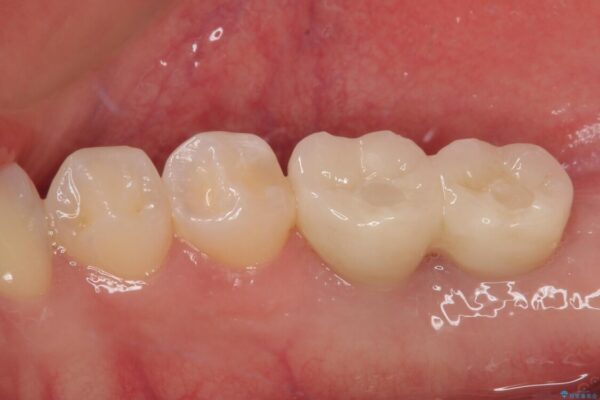

スペースが整った段階で、右下の第一大臼歯と第二大臼歯にインプラントを埋入。

その後、挺出していた右上第一大臼歯と第二大臼歯に装着されていた銀歯についても、審美性と適合性の向上を目的に、オールセラミッククラウンにやり替えました。

これにより、より自然で美しい見た目と、高い精度の咬合が得られています。

治療後

• 挺出歯を圧下してスペースを確保!目立たない部分矯正で下顎大臼歯にインプラント治療を実現 治療後画像